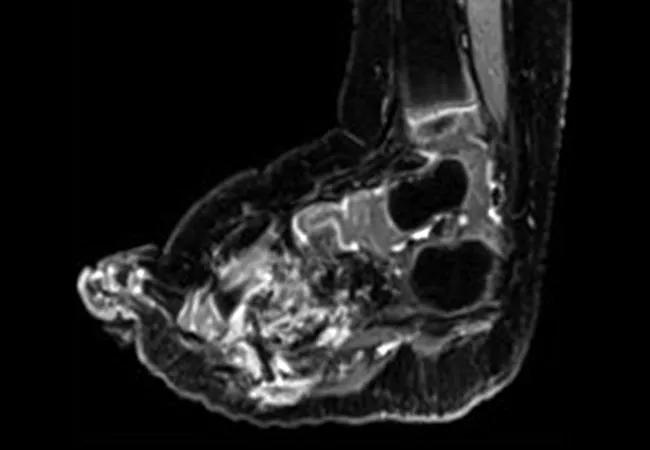

An otherwise healthy 21-month-old girl had been diagnosed with lipofibromatosis of her left foot at birth. This had progressively increased in size and affected her ability to ambulate. She was evaluated by oncologists and surgeons who recommended amputation. Next generation sequencing analysis of a biopsy specimen (FoundationOne CDx; Foundation Medicine, Cambridge, MA) identified an NCOA4-RET fusion, which was confirmed by whole genome and transcriptome analysis. Selpercatinib was initiated, and imaging after two months revealed a partial response by RECIST 1.1, with a 59% reduction in tumor volume and resolution of tumor infiltration of the metatarsals (Fig 2I-L). No adverse events were reported.

Caption: CT scans (A, B) at baseline and (C, D) after two months of treatment with selpercatinib of the left foot in a patient with an NCOA4-RET fusion–positive lipofibromatosis. Selpercatinib treatment resulted in a significant decrease in tumor burden leading to improvements in gait and locomotion.